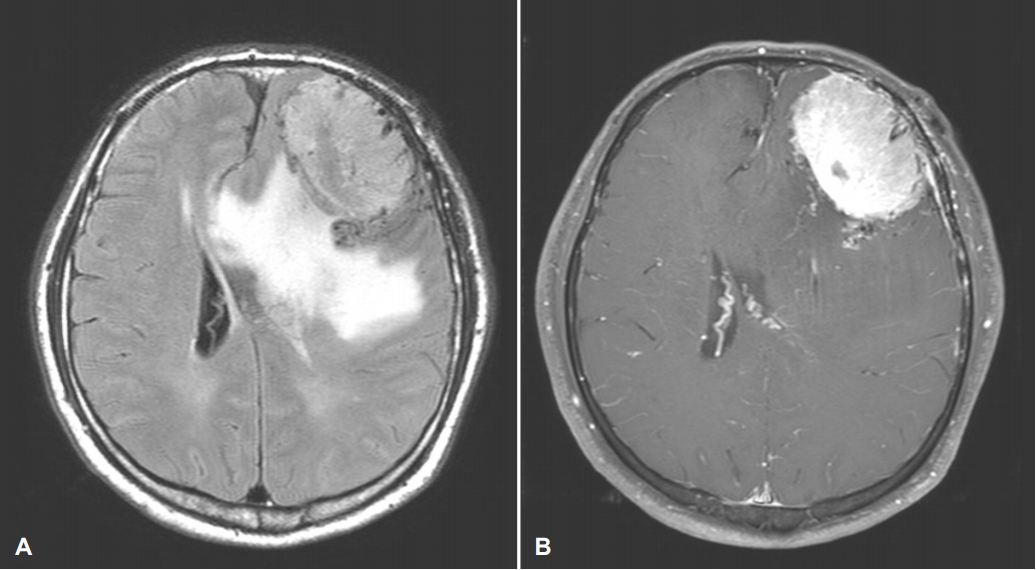

인지기능검사상 전실어증 양상의 언어기능 저하뿐 아니라 전두엽수행기능과 기억력의 저하도 동반되어 있는 상태로 뇌의 구조적 이상을 확인하기 위하여 시행한 뇌 magnetic resonance imaging에서 균일하게 조영증강되고 주변부 심한 부종을 동반한 종괴성 병변이 좌측 전두엽에서 관찰되었다(Fig.). 환자는 뇌수막종에 의하여 유발된 언어기능을 포함한 전반적 인지기능 저하로 진단 후 신경외과에서 수술을 받았다.

상기 환자의 뇌수막종은 좌측 전두엽의 궁륭부 중에서도 외측 전전두피질(lateral prefrontal cortex) 부위에 연해 넓게 위치한 관계로 브로카 영역과 주변부 손상으로 언어기능의 저하, 등쪽 외측 전전두피질의 손상으로 실행기능(executive function)의 저하를 유발한 것으로 볼 수 있다[8]. 또, 뇌수막종이 상당한 크기로 자라면서 광범위한 부종이 동반되어 있으므로 주변부 뇌 조직의 압박과 함께 관류 저하로 인하여 실어증과 기억력 저하, 전두엽실행기능 등의 인지기능에 있어 뚜렷한 기능저하를 보인 것으로 판단된다. 다만, 전두엽실행기능 중 언어기능을 활용한 검사들(COWAT, K-CWST)에 비하여 운동기능을 활용한 검사들(motor impersistence, fist-edge-pam, alternating hand movement)은 정상 결과를 보인 것으로 보아 언어기능의 손상에 의하여 언어 기억력이나 전두엽 및 실행 기능이 실제 기능저하에 비하여 검사 결과가 과장되게 평가되었을 가능성도 배제할 수 없다.